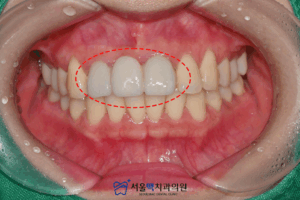

처음 내원했을 때 구강 내 사진입니다.

눈으로 보아도 인접 영구치와 색이 맞지 않으며,

보철물의 색상이 밝아

전체적으로 어색한 느낌이 드는데요.

게다가 앞니의 모양이

환자분의 앞니 모양과 다르게 둥글어

이 부분도 같이 보완하시길 원하셨습니다!